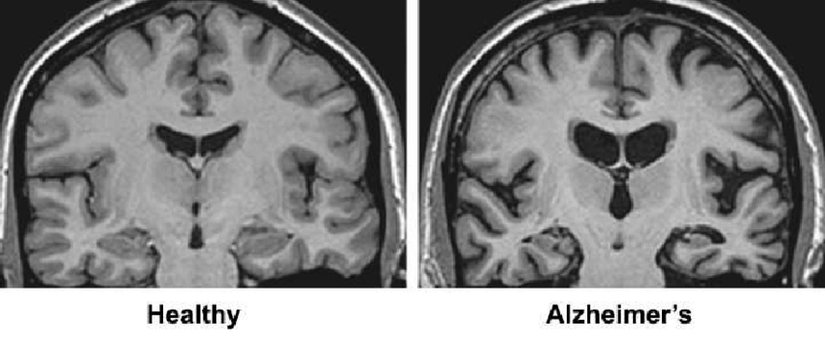

Hasar en şiddetli şekilde beyinde hafızayı kontrol eden bölgede başlar, ancak bu süreç ilk semptomlardan yıllar önce açığa çıkar. Nöron kaybı, beynin diğer bölgelerine bir miktar öngörülebilir bir şekilde yayılır. Hastalığın geç evresinde ise beyin önemli ölçüde küçülür. Araştırmacılar iki proteinin hastalık üzerinde rolüne odaklanmıştır.

Beyin Görüntülenmesi

Beyin görüntüleri artık felç, travma veya tümörler gibi bilişsel değişime neden olabilecek Alzheimer hastalığı dışındaki durumlarla ilgili gözle görülür anormallikleri saptamak için kullanılıyor. Şu anda büyük tıp merkezlerinde veya klinik deneylerde kullanılan yeni görüntüleme uygulamaları, doktorların Alzheimer'ın neden olduğu belirli beyin değişikliklerini tespit etmesini sağlayabilir.

- Manyetik Rezonans Görüntüleme (MRI) Beynin ayrıntılı görüntülerini üretmek için radyo dalgaları ve güçlü manyetik alan kullanır. MRI taramaları öncelikle diğer bulguları tespit etmek için kullanılır. Değerlendirmeler, beyin küçülmesini gösterse de, sağlanan bilgiler şu anda tanı koymaya önemli Bir değer katmıyor.